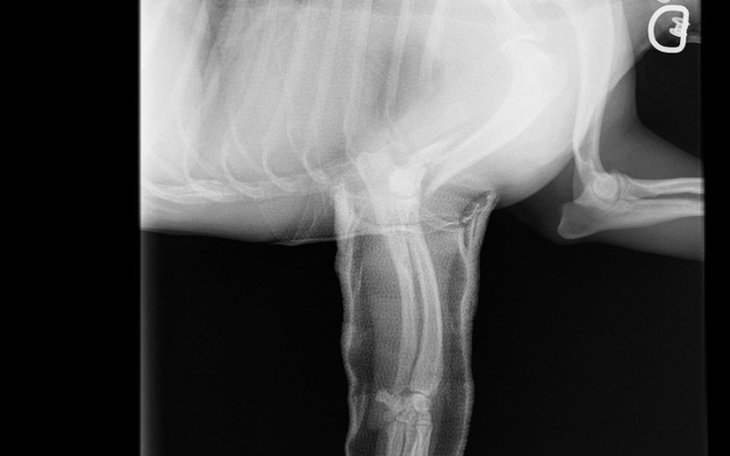

Zbieram na swojego psa, który doznał poważnych problemów z lapka. Sytuacja jest dynamiczna. Niedługo kosztowne leczeniena które zbieram.